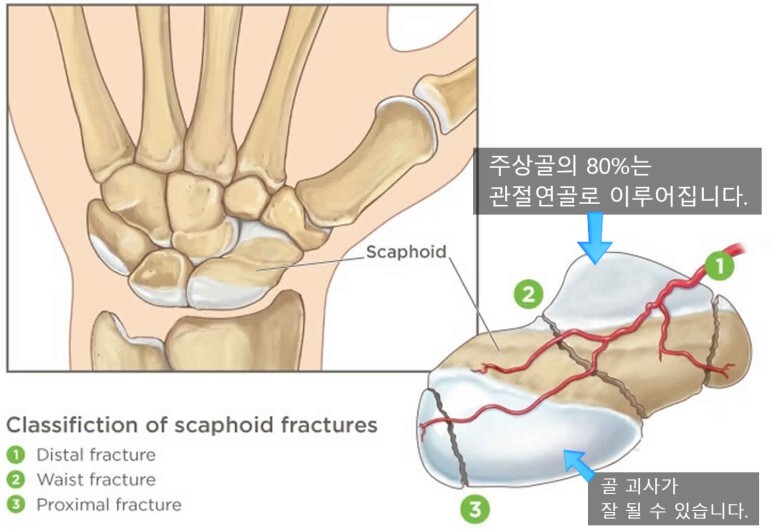

2. 주상골 골절의 분류

- 주상골 골절은 골절의 위치에 따라 대략적으로 근위부, 요부(허리, 중간), 원위부 골절로 나누며, 그 치료 방법과 예후가 달라지게됩니다.

- 근위부(손목에 가까운 부분) : 20~25%, 혈류가 끝까지 잘 가지 않을 수 있어 예후가 좋지 않습니다.

- 요부(주상골 중간) : 60%, 2달정도 CAST

- 원위부(손목에서 먼 부분) : 10~20%, 혈류가 가까워서 예후가 좋습니다.